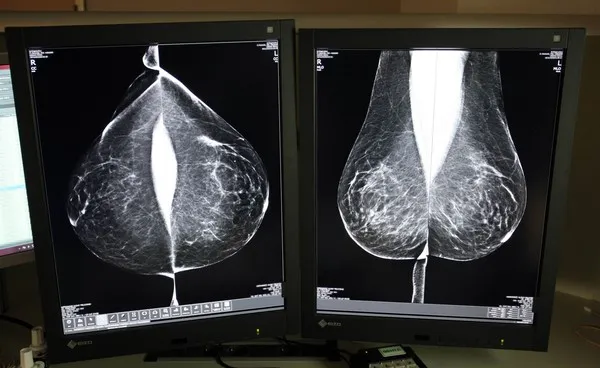

Sacyl externaliza de nuevo la doble lectura de mamografías para agilizar los tiempos del cribado que llega a más de 122.000 mujeres

La Consejería de Sanidad vuelve a externalizar el servicio de doble lectura e informe de mamografías este año para dar respuesta a la alta cobertura del Programa de Detección Precoz de Cáncer de Mama. La licitación, asciende a 1,38 millones de euros por un año, con la posibilidad de prórroga hasta un máximo de dos años, lo que elevaría el valor estimado del contrato a más de tres millones de euros. La financiación del contrato aprobado hasta la fecha se distribuye en dos anualidades: 929.200 euros en 2025 y 450.800 euros en 2026.

El programa de cribado está dirigido actualmente a mujeres con edades comprendidas entre los 45 y 74 años, franja de edad que se amplió al grupo de 69 a 74 a finales de 2023. La inclusión de este nuevo grupo ha elevado el volumen de pruebas a más de 122.000 mamografías anuales.

Desde su puesta en marcha en 1992, el programa se basa en el sistema de doble lectura, un protocolo que establece que cada mamografía sea evaluada por al menos dos radiólogos, de forma independiente, aumentando así la fiabilidad de los diagnósticos. Sin embargo, aumenta la carga de trabajo y plazos, motivo por el cual Sacyl ha optado, de nuevo, por externalizar el servicio al que el año pasado dedicó casi cuatro millones.

En 2023, último dato disponible, se realizaron un total de 122.193 mamografías, de las que 7.503 (un 6,14 por ciento) tuvieron resultado sospechoso positivo y fueron derivadas a Atención Hospitalaria para realizar el diagnóstico final. Por provincias, el porcentaje de pacientes derivadas osciló entre el 3,7 por ciento de Zamora y el 9,9 por ciento de Soria.